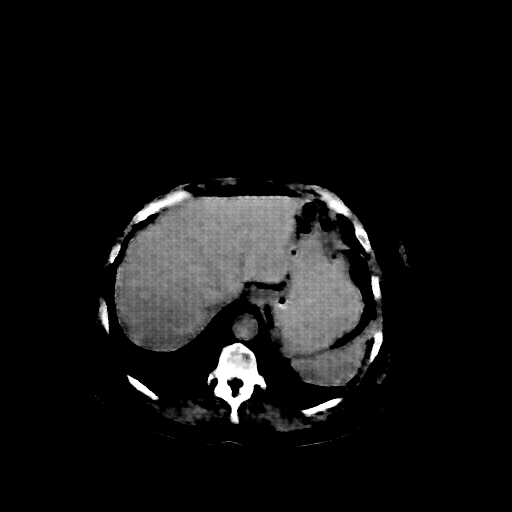

Original NATIVE CT scan (input)

Full window (WL 1023.5, WW 4095 β†’ Low βˆ’1024, High +3071)

Actual HU range: [-160.0, 240.0]